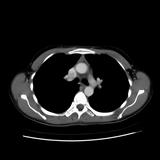

Case 8c Thymoma CT

Date: 03/27/2009

Views: 15482